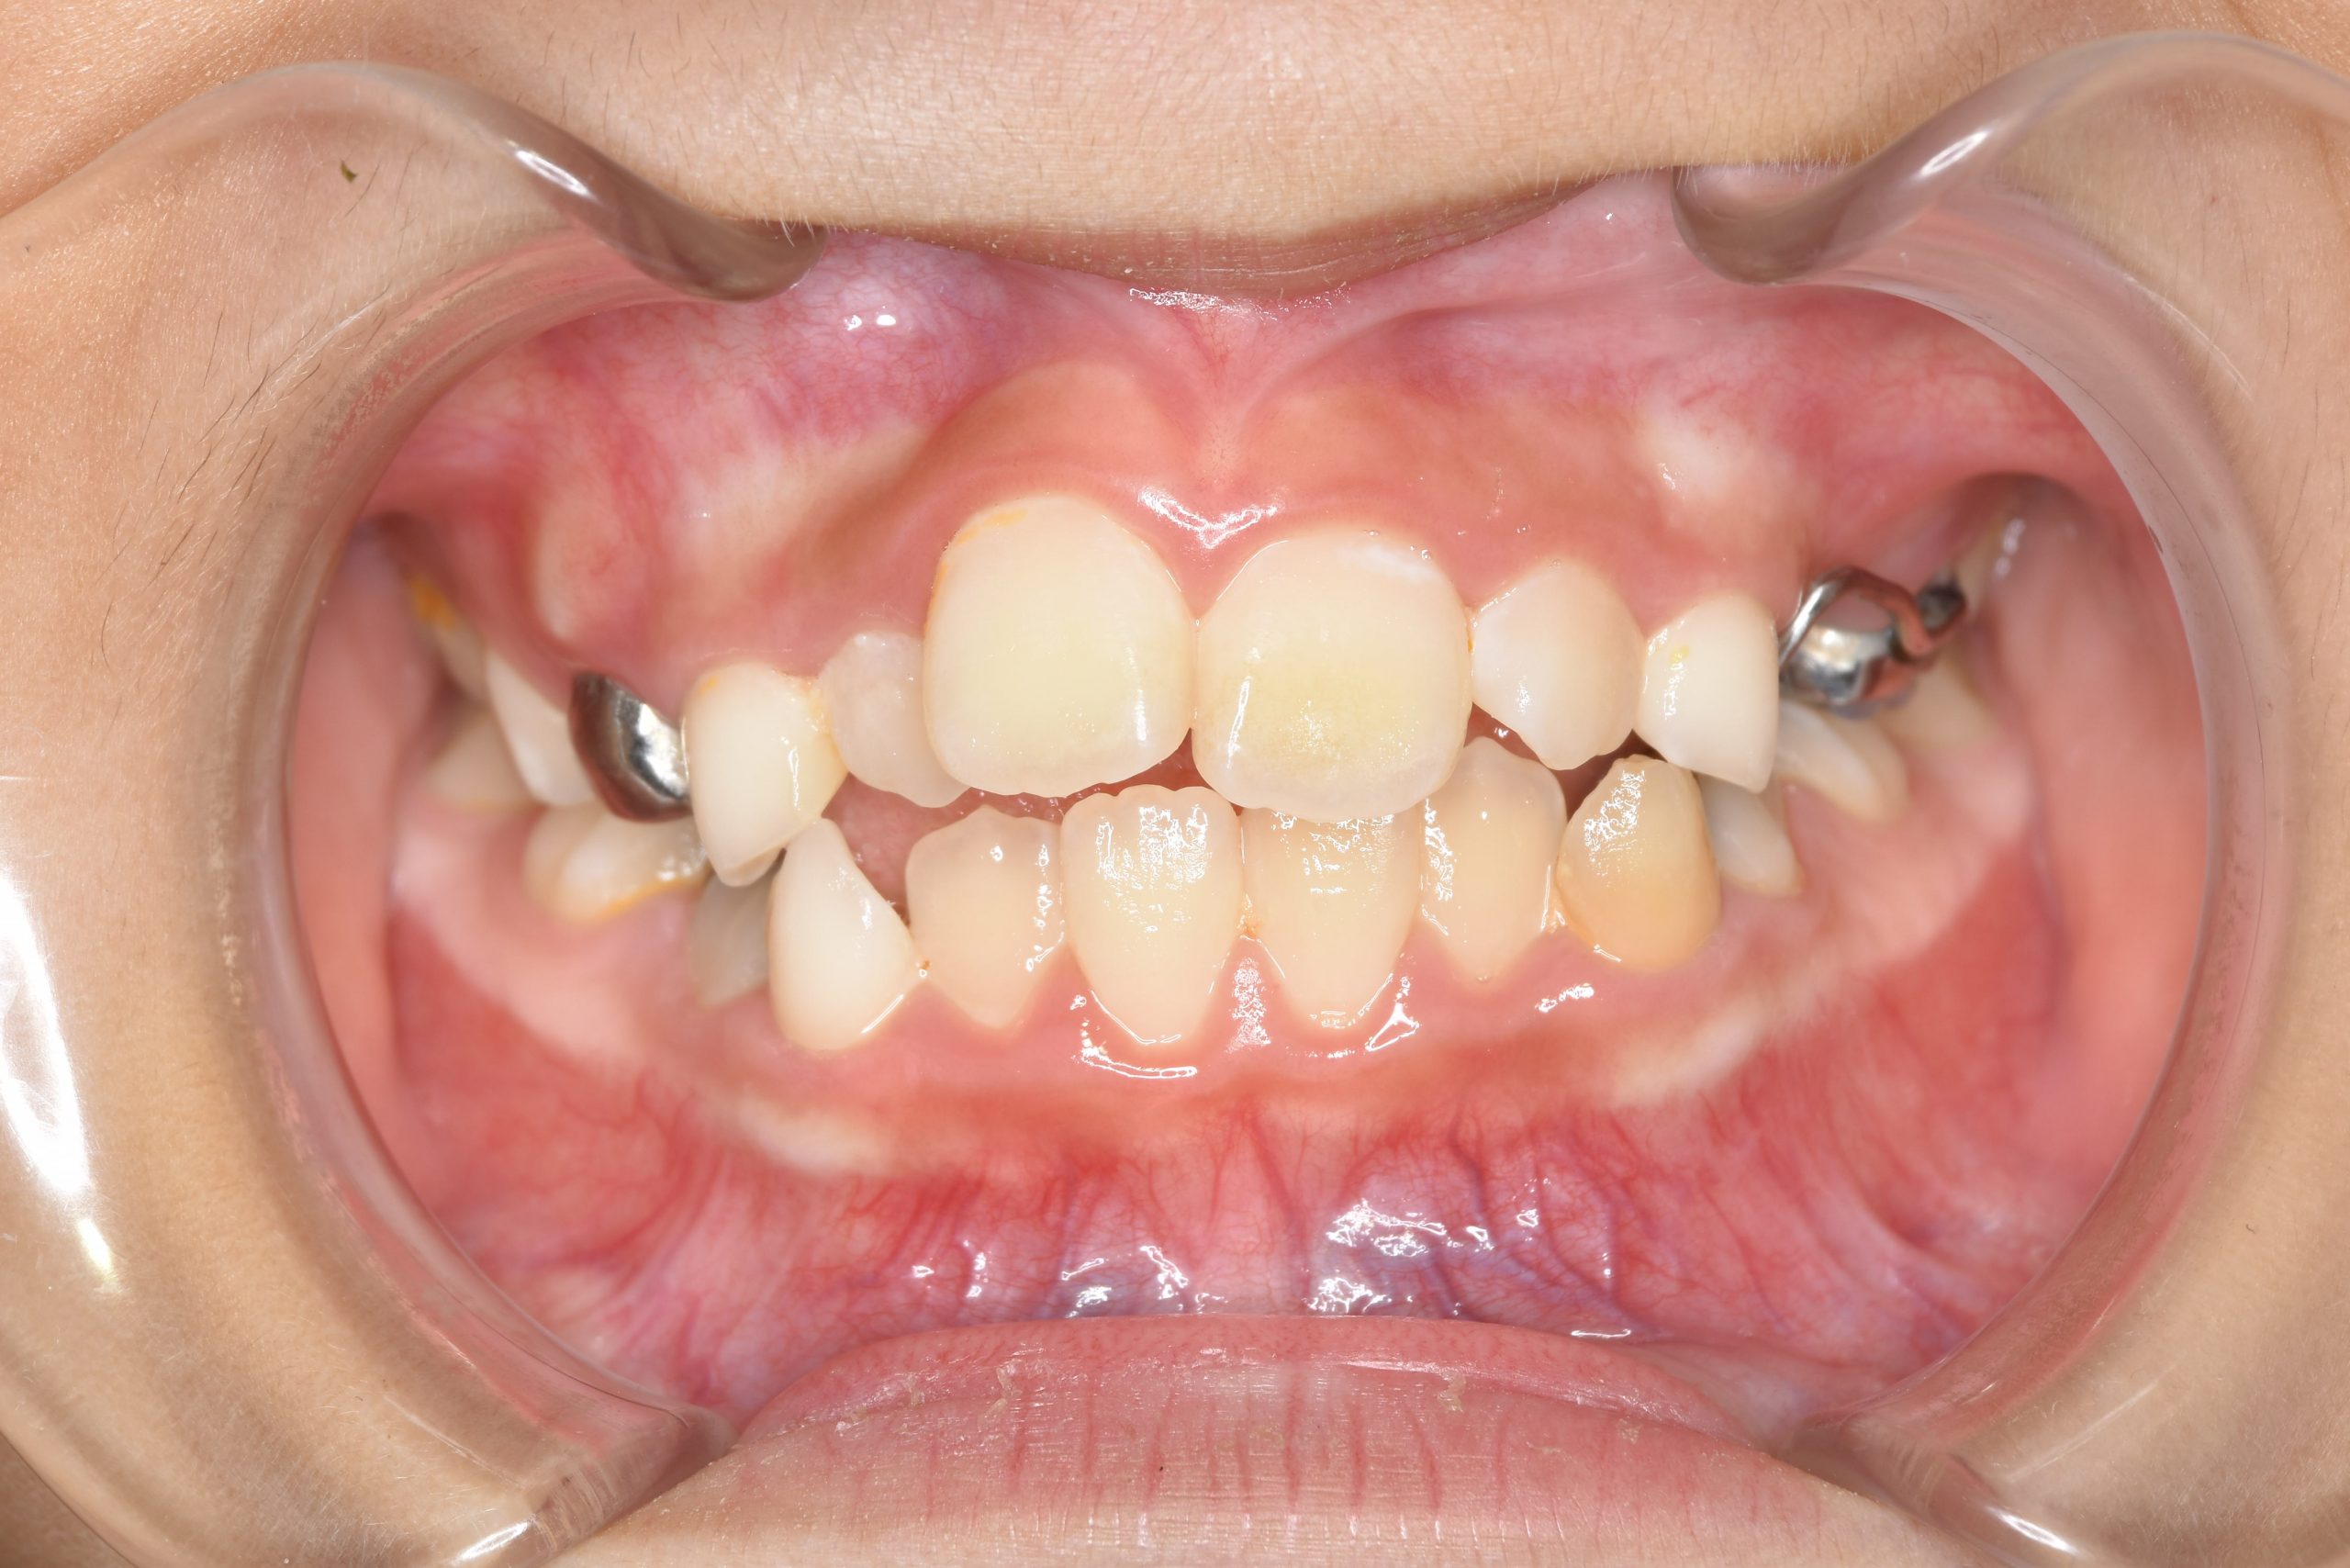

アフター

主訴 歯並び|嚙み合わせ|口呼吸

施術内容 上顎急速拡大装置と下顎リンガルアーチを用いて上下顎骨を拡大した。

その後マウスピース型矯正装置で歯牙を配列し良好な咬合を獲得した。

治癒期間 3年5ヶ月間